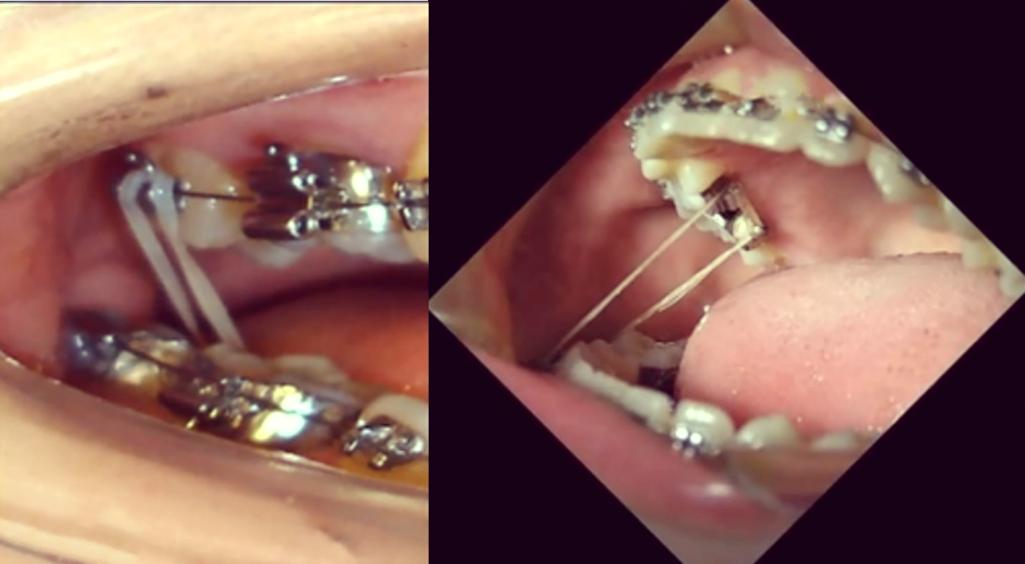

- 精准控制牵引力:根据牙齿移动距离、骨质密度,选择合适牵引力(一般不超过200g),避免“急于求成”;优先使用镍钛螺旋弹簧等持续轻力装置,而非频繁更换的弹性牵引皮圈。

- 优化牵引方向:通过数字化模拟(如正畸矫治设计软件)预测牙齿移动轨迹,确保牵引力沿牙齿长轴方向,减少侧向力对牙周及关节的损伤。

| 颌间牵引(III类/II类) | 上下牙弓间 | 牵引力过大导致颞下颌关节负荷增加;咬合干扰引发咀嚼肌紧张 | 控制牵引力≤200g;定期检查咬合,调磨早接触点 |

| 颌内牵引(对称/不对称) | 同牙弓内牙齿间 | 不对称牵引导致牙列中线偏移,咬合平衡破坏;牙齿移动速度过快引发牙周炎症 | 保持牵引对称性;使用持续轻力装置,避免频繁调整 |

| 颌外牵引(头帽式) | 牙弓与头部间 | 头帽佩戴位置不当导致颈部肌肉紧张;牵引力方向异常引发颈椎负荷增加 | 确保头帽位置居中,牵引力与牙长轴平行;避免长时间佩戴(每天≤12小时) |